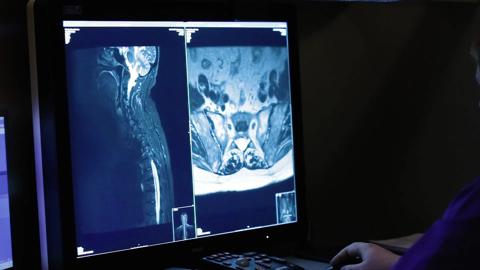

Blekinge Hospital is a general hospital located on two different sites in the south of Sweden (Karlskrona and Karlshamn). Providing high-quality healthcare is of the utmost importance at Blekinge Hospital. Therefore, the radiology department uses Barco's leading Coronis Uniti® diagnostic display systems.

“We are very satisfied with the Coronis Uniti displays as they help us deliver the best possible diagnoses,” says Ms. Kerstin Elmberg, Head of the radiology department. Her colleague Mr. Edward Azavedo, Associate Professor and Radiologist, explains: “Displays used in radiology do not have a high enough resolution to spot abnormalities in mammography images. With Coronis Uniti we see the tiniest of details. Moreover, the displays greatly enhance reading comfort.”